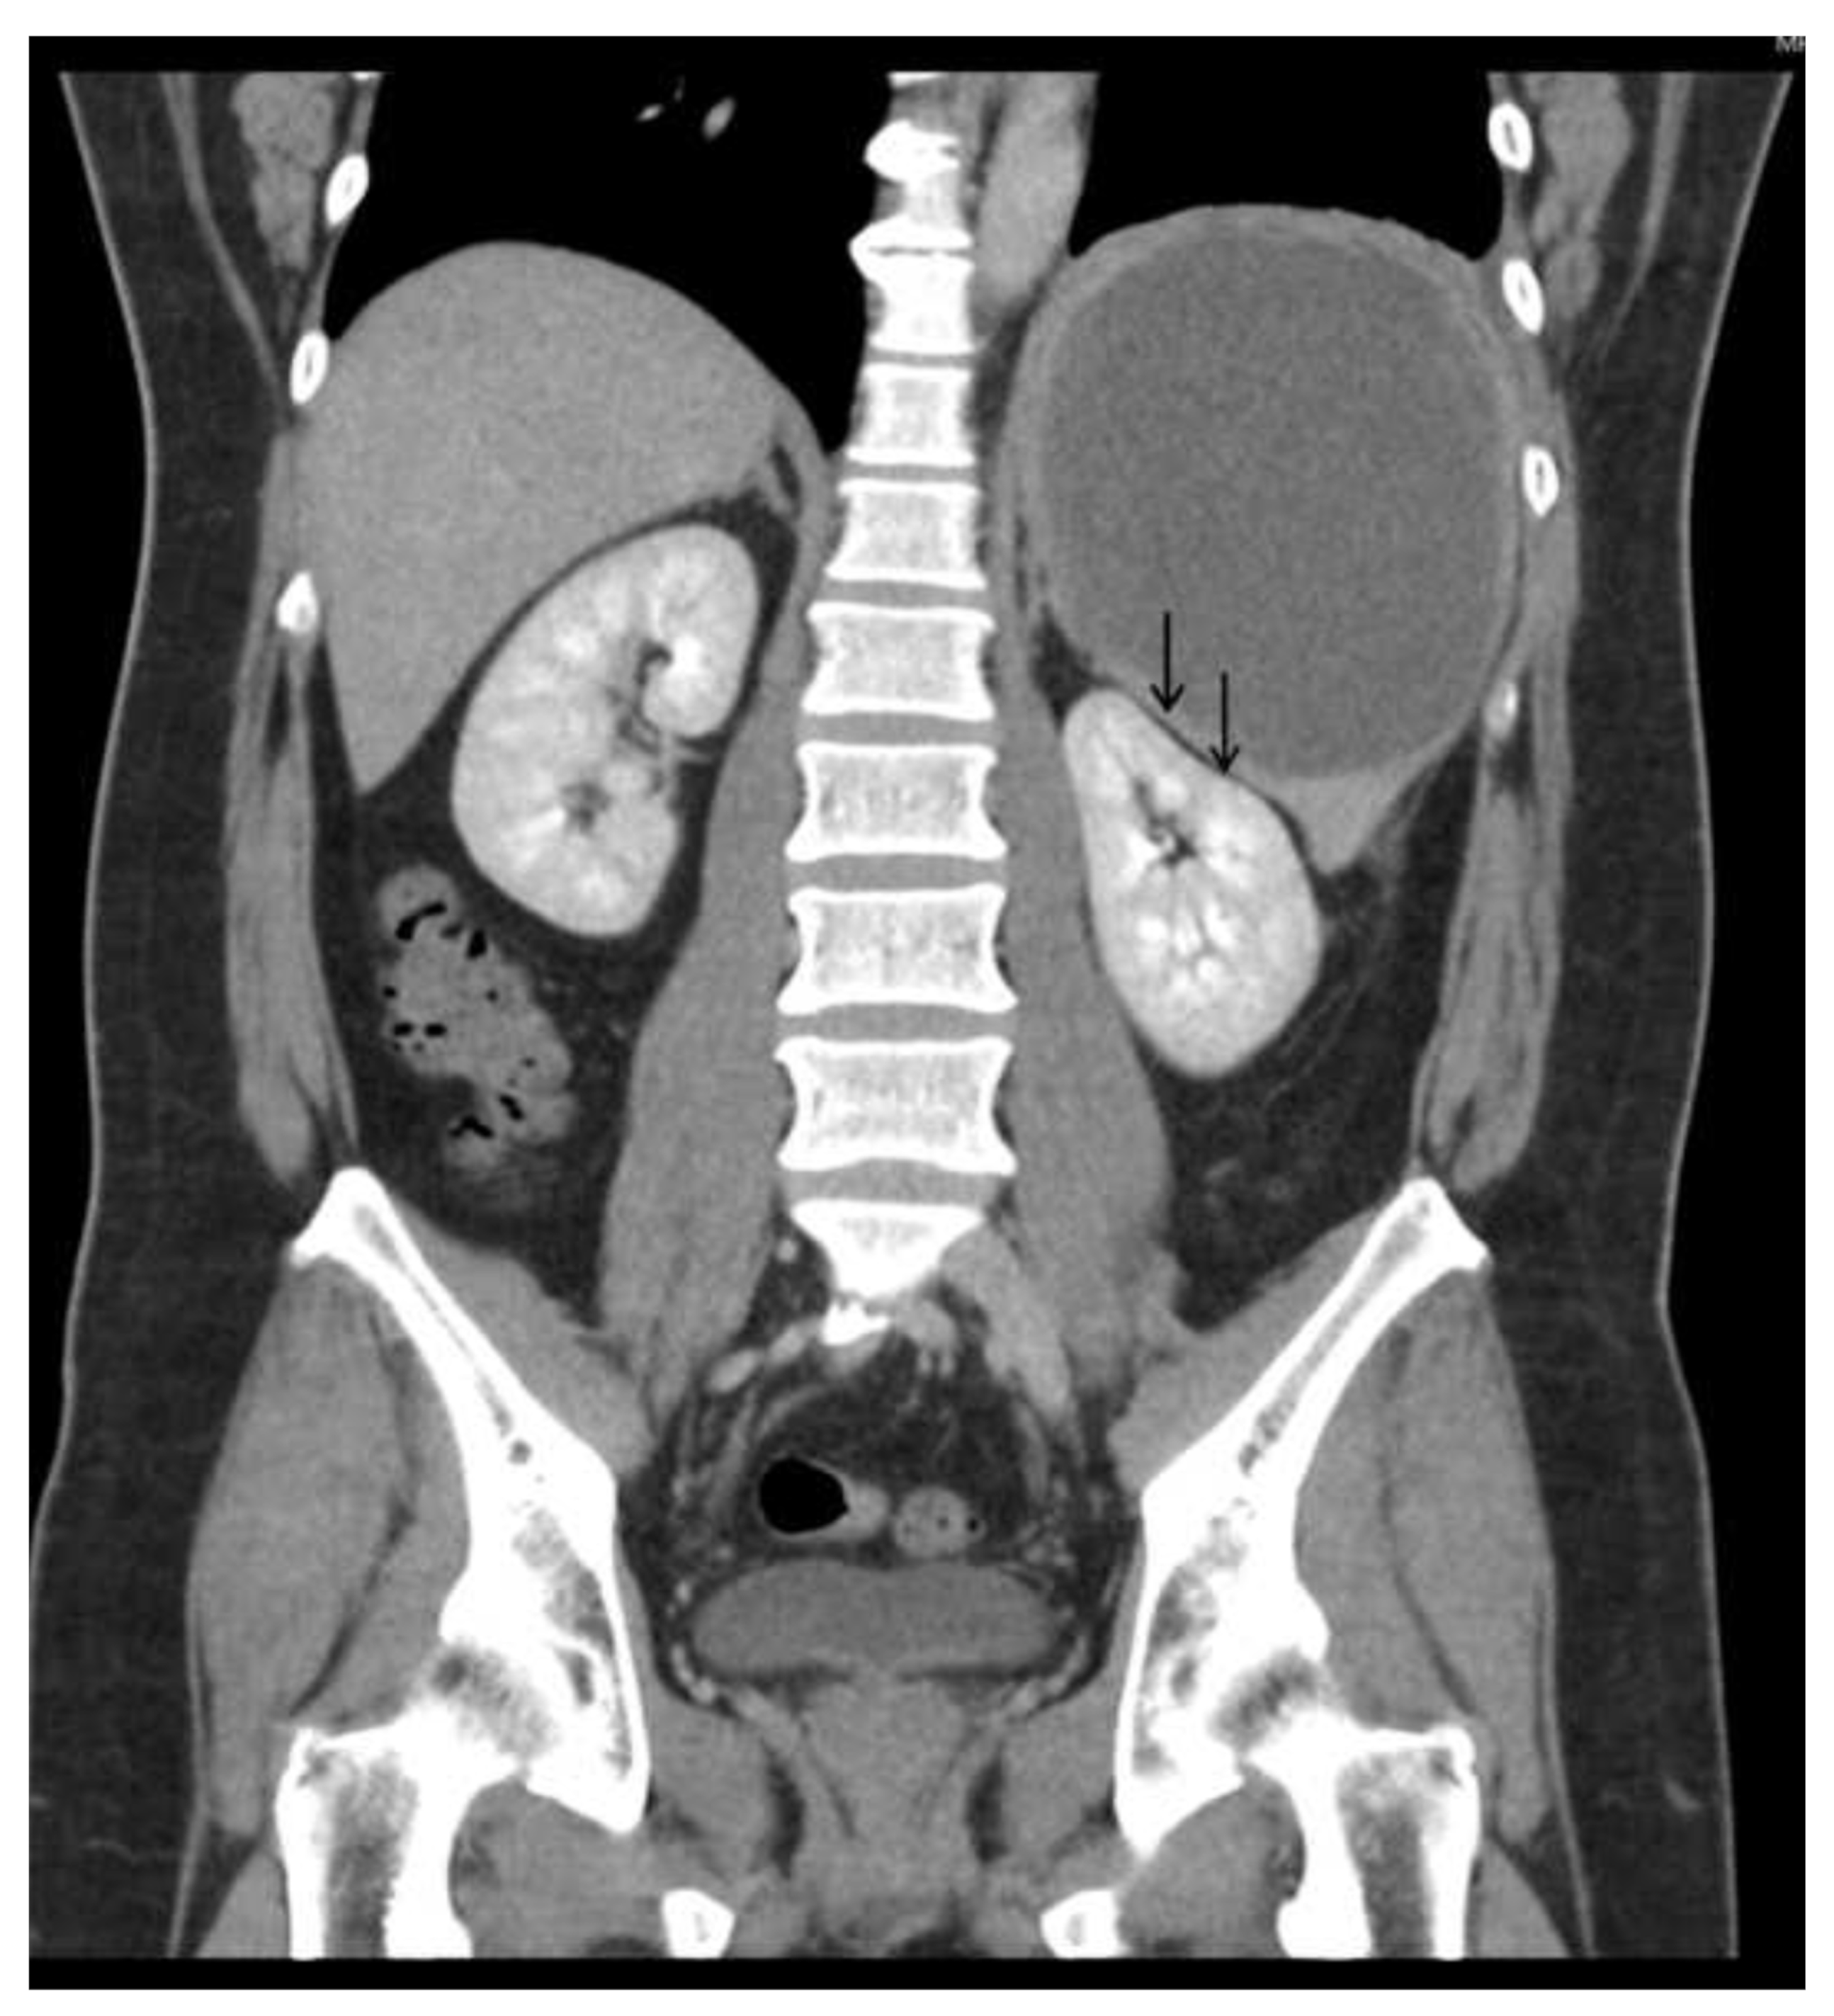

Physical examination revealed a large palpable mass with local tenderness over the LUQ. The patient’s white blood cell count was 17,000/μL, with segment neutrophil 83% and lymphocyte 10%, and platelet: 475,000/mL. An abdominal computed tomographic (CT) scan revealed a large cystic splenic mass measuring 14 cm without enhancement after contrast medium (Figure 2). The mass was pushing the left kidney inward and down (Figure 3). During the initial diagnosis, a pancreatic pseudocyst involving the spleen was suspected, and the patient received an emergency splenectomy because of the rapid growth of the mass and severe pain.

Figure 3.

Abdominal CT scan showed the mass was pushing the left kidney inward and down.